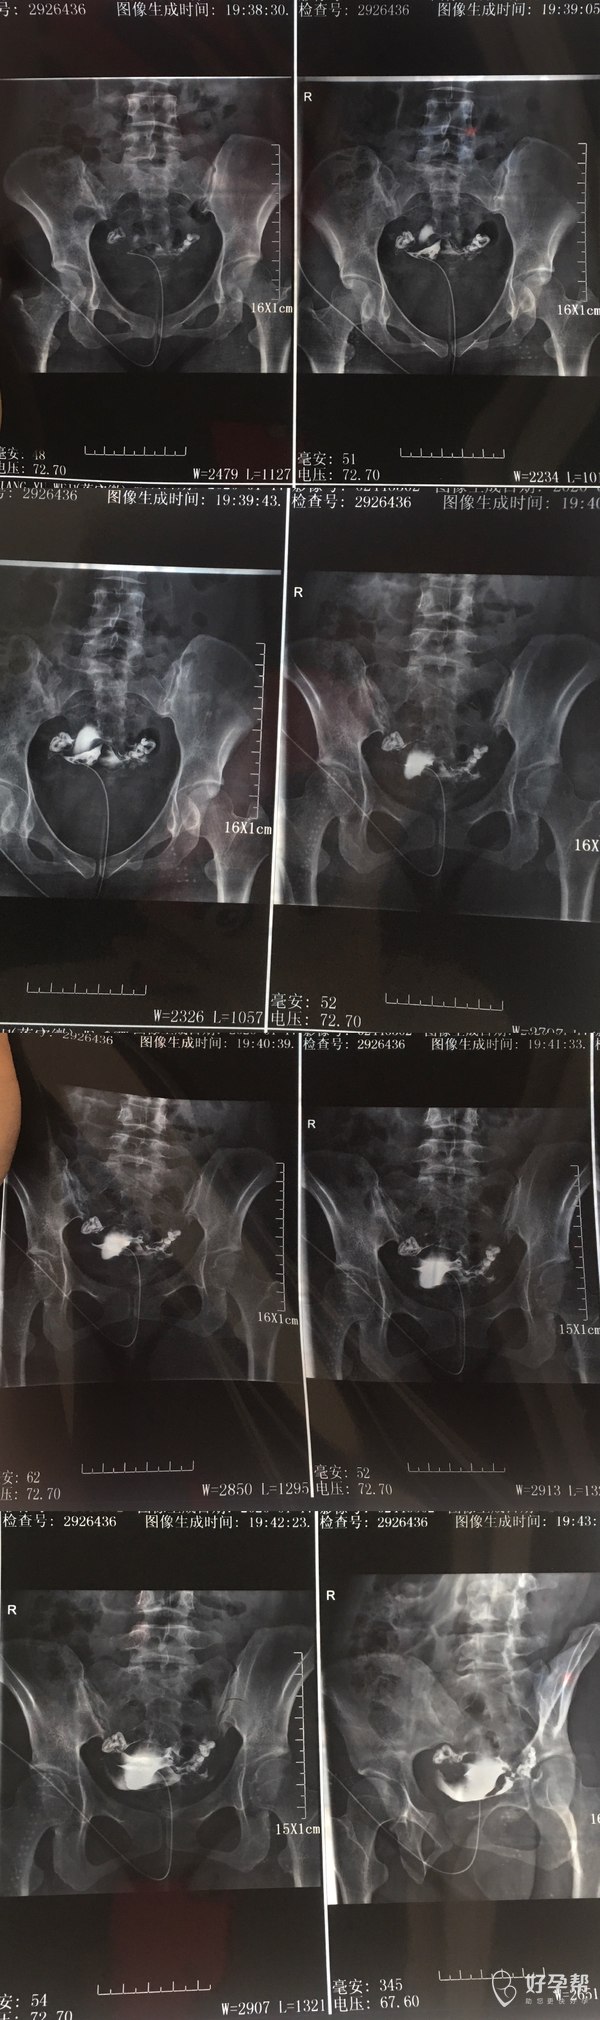

希望可以帮我看见输卵管造影片

你好,输卵管是通畅的,但是两侧都比较迂曲,可以先试孕几个月